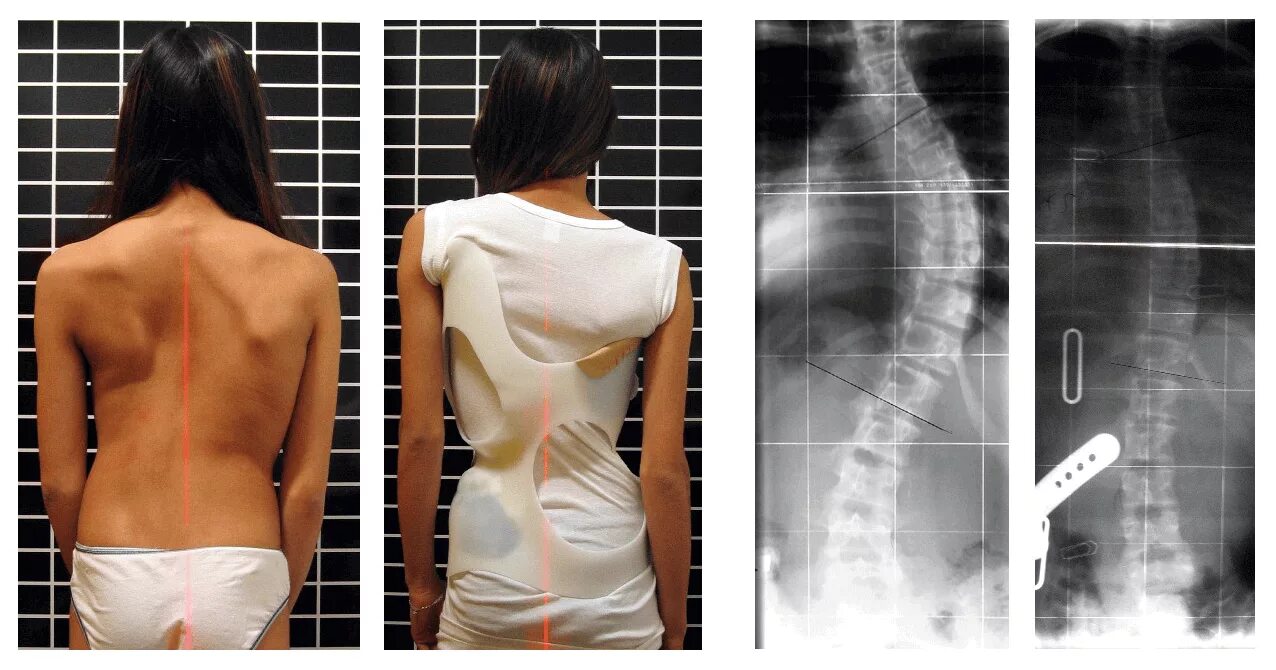

Грудопоясничный сколиоз 3 степени. 3 степени искревле искривление позвоночника. s образный кифосколиоз грудного отдела позвоночника. кифосколиоз грудного отдела позвоночника 2.Сколиоз позвоночника у детей 3 степени. искривление позвоночника у детей сколиоз 3 степени. диспластический сколиоз 2 степени. искривление позвоночника 2 степени у детей.Сколиозе степень искривления позвоночника. искривление позвоночника первой степени.Врождённый сколиоз у ребенка 3 степени. сколиоз позвоночника 3 степени. сколиоз позвоночника 3 степени инвалидность. сколиозе степень искривления позвоночника.Сколиоз позвоночника первая стадия. сколиоз позвоночника 2-3 степени. сколиоз позвоночника 1 степени градусы. 3 стадия сколиоза позвоночника.Грудопоясничный сколиоз 3 степени s образный.Степени сколиоза позвоночника по градусам у детей. 1 степень сколиоза по чаклину рентген. позвоночник при сколиозе 2 степени. сколиоз позвоночника 4 степени рентген.Сколиоз 3 степени лечениеСколиоз позвоночника 3 степени инвалидность. сколиотическая деформация позвоночника 40 градусов. инвалидность сколиоз 2 степени. s образный грудопоясничный сколиоз 2 степени инвалидность.Сколиоз спины 1 степени. сиомиоз позвоночника 1 степени. симптомы сколиоз 1 степени у детей. лечится ли сколиоз 1 степени у подростков.Искривление позвоночника у детей сколиоз 3 степени. рёберный горб сколиоз 2 степени.Сколиоз позвоночника 2 степени. инвалидность сколиоз 2 степени. сколиоз 3 степени инвалидность.Искривление позвоночника 2 степени. дугообразный сколиоз 2 степени. ii степень сколиоза характеризуется. фиксированный сколиоз 2 степени.Сколиоз 3 степени лечениеКорсет шено для шейермана мау. искривление позвоночника шейермана мау. сколиоз болезнь шейермана мау. корсет шено шейерман мао.Сколиоз поясничного отдела 3 степени. сколиоз 3 степени снимок. сколиоз 3 степени рентген после операции. диспластический сколиоз 3 степени.Корсет шено сколиолоджик. корсет функционально-корригирующий шено. корсет шено от сколиоза. корсет шено сколиоз 2 степени.Сколиоз позвоночника 4 степени. грудопоясничный сколиоз 4 степени. кифосколиоз грудного отдела 4 степени. кифосколиоз 2 грудного отдела.Сколиоз 3 степени лечениеСтепени деформации позвоночника при сколиозе. дугообразный сколиоз 1 степени. сколиоз 1 степени грудного отдела и поясничного отдела позвоночника. диагноз сколиоз 1 степени.3 степени искривления осанки. формы сколиоза позвоночника. s образный сколиоз 3 степени. сколиоз позвоночника вид сбоку.Тораколюмбальный сколиоз. ишиалгический сколиоз. сколиоз позвоночника у подростков 14 лет. раймонди сколиоз.Сколиоз 4 степени корсет шено. корсет шено s образный сколиоз. корсет эббота-шено. грудопоясничный сколиоз 3 степени рентген.Операция на сколиоз 2 степени. сколиоз операция рентген. операция на позвоночник сколиоз 2 степени. сколиоз 4 степени рентген.Сколиоз 3 степени лечениеСколиотическая деформация позвоночника. врожденный сколиоз позвоночника. тораколюмбальный сколиоз. правосторонний сколиоз th6-th7.Сколиоз позвоночника 1 степени. левосторонний сколиоз 2й степени. правосторонний сколиоз 1 ст. правосторонний и левосторонний сколиоз.Сколиоз 1 степени сбоку. сколиоз 10 градусов рентген.Корсет шено при сколиозе 4 степени. корсет шено сколиоз 2-3 степени. корсет шено s образный сколиоз.Сколиотическая деформация позвоночника. сколиотическая деформации позвоночника 1-2 степени. кифосколиоз грудного отдела позвоночника.Искривление позвоночника сколиоз. идиопатический сколиоз грудного отдела позвоночника. сколиотическая деформация позвоночника. сколиоз поясничного отдела 3 степени.S образное искривление позвоночника 3 степени. сколиоз поясничного отдела позвоночника по степеням. s образный сколиоз 1 степени по чаклину. сколиоз 2 степени угол искривления.Сколиотическая дуга. дугообразное сколиотическое искривление. сколиоз с 3 дугами искривления. сколиозы 4 степени деформации.Сколиоз 1 степени симптомы. искривление позвоночника 1 степени. этапы сколиоза.Грудопоясничный сколиоз 3 степени s образный. корсет шено s образный сколиоз. сколиоз позвоночника 2 степени.Корсет шено шейерман мау. корсет шено сколиоз 2-3 степени. корсет шено для шейермана мау. сколиоз 3 степени корсет шено.Корсет шено шейерман мао. сколиоз корсет шено. корсет шено кифоз. сколиоз 3 степени корсет шено.Идиопатический правосторонний грудопоясничный сколиоз 2 степени. идиопатический правосторонний грудопоясничный сколиоз 1 степени. идиопатический сколиоз грудного отдела позвоночника. идиопатический грудопоясничный сколиоз 3 степени.Сколиоз корсет шено. сколиоз в подростковом возрасте.Корсет шено кифоз. корсет шено и гимнастика шрот. корсет шено s образный сколиоз. корсет шено при кифозе.Сколиоз 3 степени корсет шено. корсет шено сколиоз 2 степени. корсет шено s образный сколиоз. s образный сколиоз 2 степени грудного отдела.Презентация на тему сколиоз. сообщение на тему сколиоз. сообщение о искривлении позвоночника. сколиоз доклад по биологии.Методики лечения сколиоза. рекомендации врача при сколиозе. сколиоз 1 степени лечится.Сколиоз позвоночника 2-3 степени. сколиоз 2 степени по чаклину. сколиоз позвоночника 1 степени. левосторонний сколиоз 3-4 степени.Градусы искривления позвоночника. 25 градусов искривление позвоночника. сколиоз позвоночника 25 градусов. искривление позвоночника 11 градусов.Сколиоз кифоз грудного отдела. позвоночник сколиоз грудного отдела позвоночника. сколиоз кифоз 3 степени.Искривление позвоночника 3 степени. искривление позвоночника 2 степени.Нейрофиброматоз сколиоз. миопатический сколиоз. клиника сколиоза позвоночника.Сколиоз корсет шено. сколиоз 3 степени корсет шено. корсет шено сколиоз 2-3 степени. сколиоз 4 степени корсет шено.Операция харрингтона сколиоз. метод харрингтона сколиоз рентген. дистрактор харрингтона. сколиоз 4 степени рентген.Кифосколиоз грудного отдела позвоночника 1. правосторонний и левосторонний сколиоз. идиопатический сколиоз грудного отдела позвоночника. кифосколиоз пояснично крестцового отдела.Идиопатический грудопоясничный сколиоз. идиопатический грудопоясничный сколиоз 1 степени. юношеский сколиоз 2-3 степени.Сколиоз 3 степени корсет шено. шено при сколиозе 4 степени. корсет шено сколиоз 2-3 степени. сколиоз 4 степени корсет шено.Сколиоз боковое искривление позвоночника. идиопатический сколиоз 3 степени. диспластический кифосколиоз. идиопатический s-образный сколиоз 4 степени..Сколиоз 3 степени операция. сколиоз 4 степени рентген операция. операция на позвоночник сколиоз 3 степени. операция харрингтона сколиоз.Паралитический сколиоз. сколиоз кифоз 3 степени. миопатический сколиоз. кифоз позвоночника 4 степени.Сколиоз 3 степени лечениеСколиоз позвоночника горб. рёберный горб сколиоз 2 степени. рёберный горб сколиоз 3-4 степени. сколиоз позвоночника схема.Сколиоз грудного отдела позвоночника. боковое искривление позвоночника. сколиоз позвоночника 2 степени.Кифосколиоз грудного отдела позвоночника. сколиотическая деформация позвоночника. сколиоз позвоночника сколиоз.Корсет шено кифоз. корсет шено для позвоночника кифоз. корсет шено сколиоз 2 степени. корсеты шато при сколеозе.Статистический сколиоз. упражнения для s образного сколиоза 3 степени. стабильность позвоночника.Сколиоз позвоночника правосторонний 2 степени. s образный сколиоз грудного и поясничного отдела 2 степени. левосторонний грудопоясничный сколиоз. левосторонний s образный сколиозе 2 степени.Сколиоз 1-2 степени. сколиоз 2 степени презентация. паралитический сколиоз.Сколиоз 2 степени искривление 17 градусов. фиксированный сколиоз 2 степени при угле искривления 17 градусов. сколиоз отклонение 1 степень. угол искривления при сколиозе 2 степени.Сколиоз 3 степени лечениеСколиоз 3 степени лечениеСколиоз позвоночника влево. отклонение оси позвоночника вправо в грудном отделе. сколиоз отклонение 1 степень. сколиоз позвоночника первая стадия.Дистрактор харрингтона. сколиоз 4 степени рентген. операция на позвоночнике сколиоз 4 степени. сколиоз позвоночника 4 степени рентген.Анталгический сколиоз. левосторонний грудопоясничный сколиоз. сколиоз грудного отдела позвоночника 2 степени. s образный сколиоз грудного отдела позвоночника.Корсет эббота-шено. корсет шино шино. дикуль корсет шено. сколиоз 3 степени корсет шено.Сколиоз описание. z образный сколиоз. сколиотическая болезнь позвоночника.Грудопоясничный сколиоз 3 степени s образный. сколиоз позвоночника у взрослых 3 степени. s образный грудопоясничный сколиоз 2 степени. s образный сколиоз 2 степени поясничного отдела.Идиопатический s образный сколиоз. с образный сколиоз 4 степени. s образное искривление позвоночника. сколиоз 2 степени s образный идиопатический.